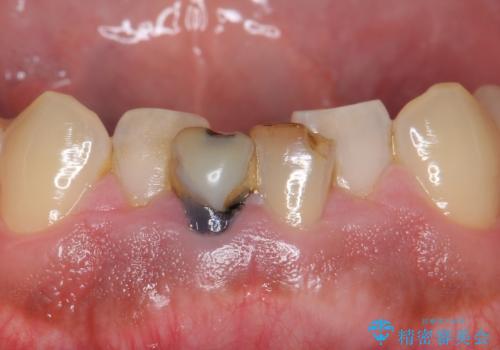

- 下の前歯の色が気になることを主訴に来院された患者様です。

下の前歯は金属の土台により黒くなり、隣の歯も神経が死んで暗く変色していました。

神経が死んでいる歯の根管治療を行った後、セラミッククラウンによる補綴治療を行いました。

- ¥320,000 (根管治療×1、土台×2、仮歯×2、クラウン×2)費用は治療当時の料金となります